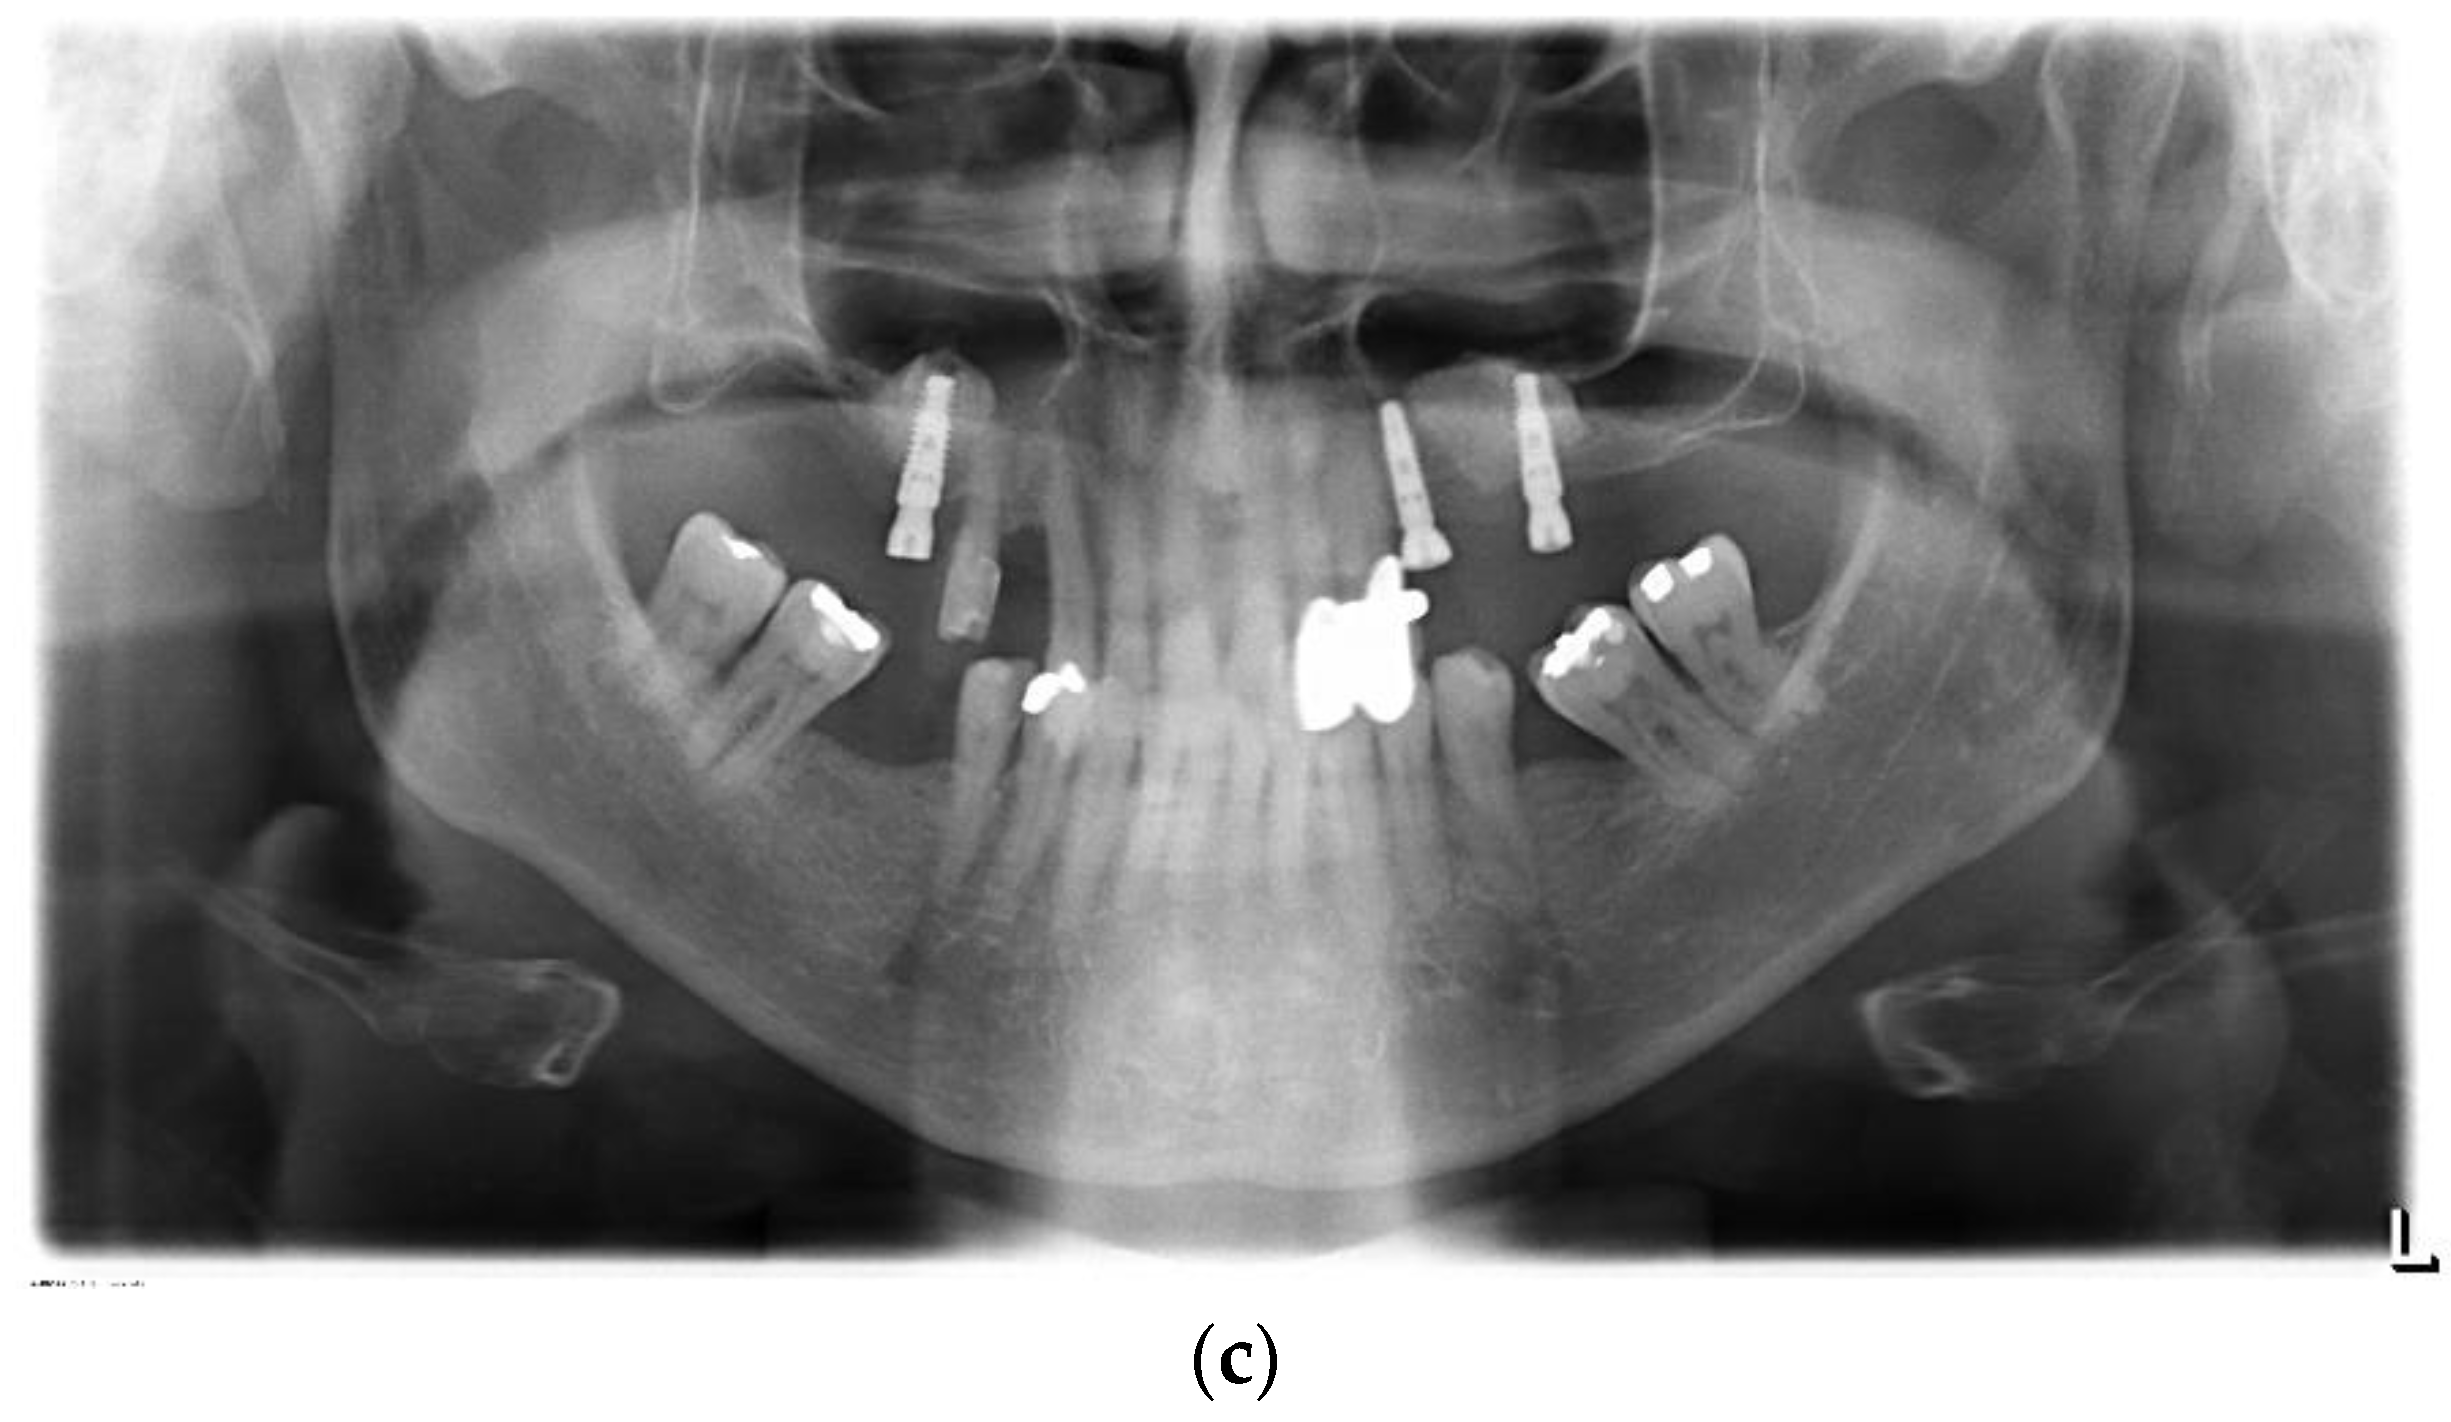

Following the uncovering of the implants, the panoramic radiograph showed a sufficient osseointegration of all implants. No sign of an inflammation of the maxillary sinuses was found. The scaffolds were found to be sufficiently osseointegrated. No osteolytic areas could be observed (Figure 5c).

After a healing period of five months, the second stage implant surgery for uncovering the implants followed. In local anesthesia (Ultracain DS, Sanofi Aventis Deutschland, Frankfurt, Germany), a palatal incision was performed, and the mucosal flaps were deflected to uncover the implants. Healing abutments (SIC 3.3 × 4 mm and 3.3 × 3 mm, SIC invent AG, Basel, Switzerland) were fixed. Wound closure again was performed with non-absorbable sutures (Prolene monofil 5-0, Johnson & Johnson Medical GmbH, Ethicon Deutschland, Norderstedt, Germany). Postoperatively, a panoramic radiograph was carried out to examine the osseointegration of the implants.